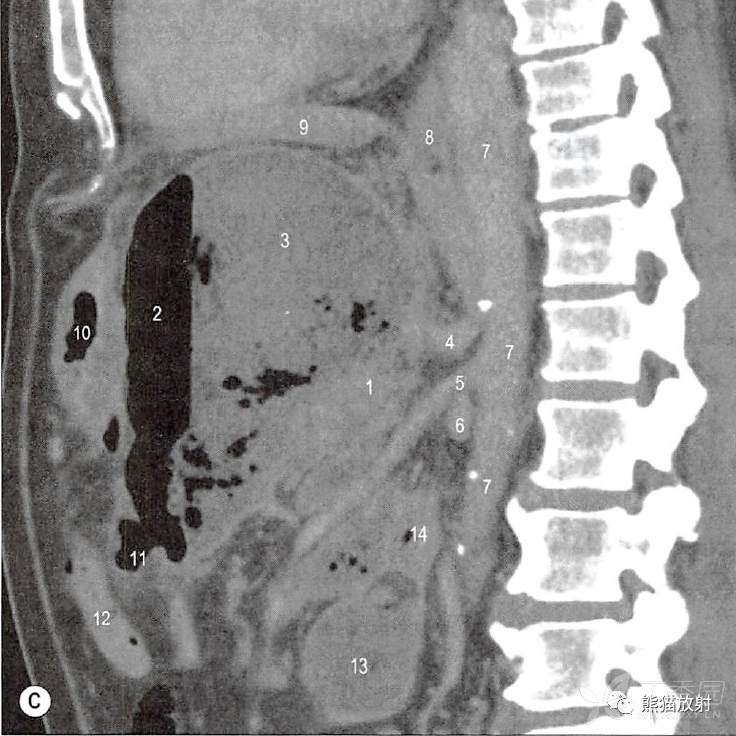

一例58岁慢性胰腺炎和胰周假性囊肿男性患者。

口服和静脉注射增强对比剂计算机扫描(CT轴位和矢状位)。

假性囊肿,包含气体和液体,胰周间隙扩大。融合筋膜的边界因为慢性炎症增厚,容易可见。

D.经左肾门矢状切面;1.胰体;2.积液;2.左肾实质;3.胃底(口服对比剂);4.胃体;5.左上肾周筋膜与胰腺后筋膜融合;6.左肾前筋膜与左结肠系膜右叶融合(Toldt筋膜) ;7.十二指肠升部;8.左肾实质;9.脾